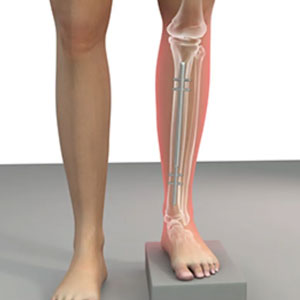

Ilizarov frames provide a versatile fixation system for the management of bony defo...

Read details